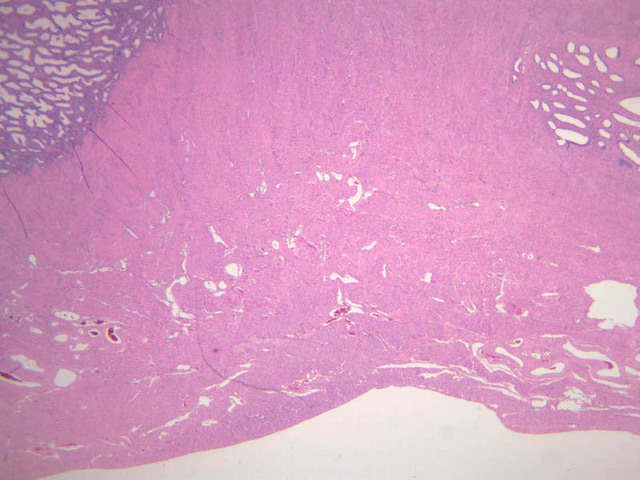

Secretory Phase

This phase occurs on days 15 to 27 and corresponds to the ovarian luteal phase characterized by rising levels of progesterone. The epithelial cells begin to secrete a mucoid fluid rich in nutrients, especially glycogen. The glands become highly coiled and folded and toward the end, very distended. The density of the stroma lessens as it becomes edematous. (slides B-99 [2.5x, 10x, 20x, 40x] [2.5x, 10x, 20x, 40x]; B-100 [1x, 2.5x] [2.5x, 10x, 20x, 40x] [2.5x, 10x, 20x, 40x])